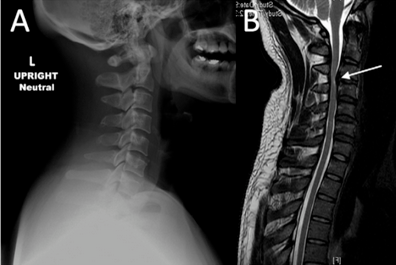

颈椎前缘的条状高信号影,终于知道是什么啦!

颈椎前缘的条状高信号影,终于知道是什么啦~~